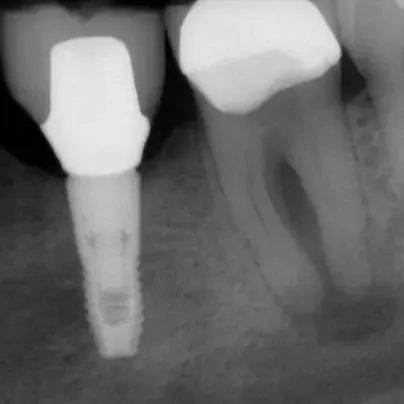

Fall 1: Revisionsbehandlung

Kontrolle nach Wurzelfüllung